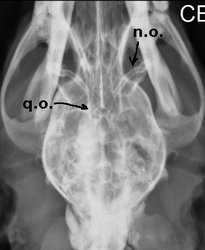

Los nervios ópticos (n.o.) y el quiasma óptico (q.o) se pueden observar en una ventriculografía (radiografía con contraste yodado aplicado en cisterna magna). Recordemos que los nervios ópticos están envueltos por meninges y por ende por líquido cefalorraquídeo.